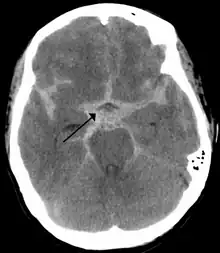

T1-weighted MRI scans (with contrast) of the same brain slice at monthly intervals. Bright spots indicate active lesions of multiple sclerosis.

Photo credit: Public domain (U.S. Brookhaven National Laboratory)